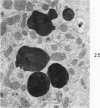

The beige mouse is a homolog of Chediak-Higashi syndrome, a disorder which is characterized by the presence of enlarged (anomalous) lysosomes in many cell types. In kidney, anomalous lysosomes are present in cells of the proximal convoluted tubules. In this study, the degradation of injected horseradish peroxidase (HRP) in lysosomes was studied in both the convoluted (S1-S2) and straight (S3) segments of the proximal tubules of beige and control (C57 B1) mice. Tissues were removed at intervals from 18 hours to 7 days after HRP injection. Peroxidase activity was visualized for light and electron microscopy by incubating sections in diaminobenzidine medium. No differences in the rate of degradation of HRP were demonstrable between anomalous lysosomes in S1-S2 cells of beige kidney and those in controls. In both animals, HRP was demonstrable in these lysosomes at 18 and 36 hours but not at 48 hours after injection. By electron microscopy, reaction product appeared as a flocculent precipitate distributed uniformly throughout the lysosome. In contrast to those of S1-S2 cells, lysosomes of beige S3 cells degraded HRP much more slowly than did those of control mice. In controls, HRP was demonstrable in S3 lysosomes at 18 hours but not at 48 hours after injection. In beige mouse kidney HRP was demonstrable in many S3 lysosomes at 48 hours, and it persisted in some lysosomes as long as 5 days after injection. These findings indicate that beige S3 lysosomes are defective in degrading protein. As reported recently, these lysosomes are also markedly enlarged and altered in content. They appear to arise as part of a renal lesion of unknown pathogenesis which is confined to the S3 segments of the proximal tubules. The slower rate of degradation of protein appears to be another manifestation of the alteration in these lysosomes.